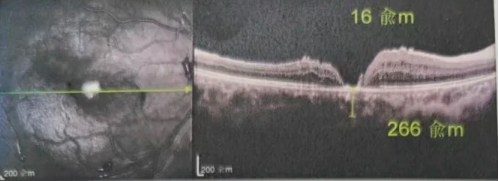

最讓吳爺爺難以置信的是:術后只需保持平躺24小時!第二天復查時,眼底鏡及OCT檢查清晰顯示——那個折磨了他大半年的大裂孔,竟然閉合了!且吳爺爺的右眼視力有了明顯的改善,術后3天已經可以看到 0.15。

黃斑裂孔

李海波博士后表示:如果來得更早一些,他的視力還可以恢復得更好。但現在的治療結果對于經歷過兩次失敗手術和漫長煎熬的他而言,已是奇跡。